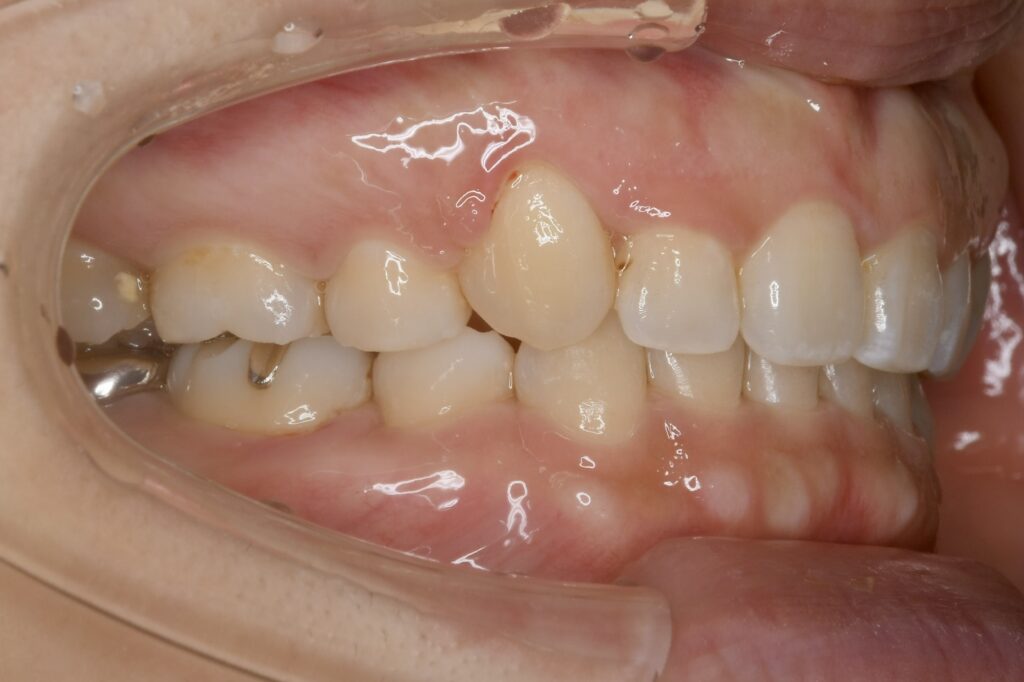

32歳 女性 治療期間:1年7ヶ月

AFTER

• マウスピース装着時

診断名・主な症状 叢生を伴う上顎前突

治療内容 上下とも歯を2本抜いて、上の前歯を後方に引きながら、でこぼこを治しました。

使用装置 マウスピース矯正装置(インビザライン)

抜歯部位 上 両側4番目

下 右側4番目、左側5番目

治療期間 1年7ヶ月